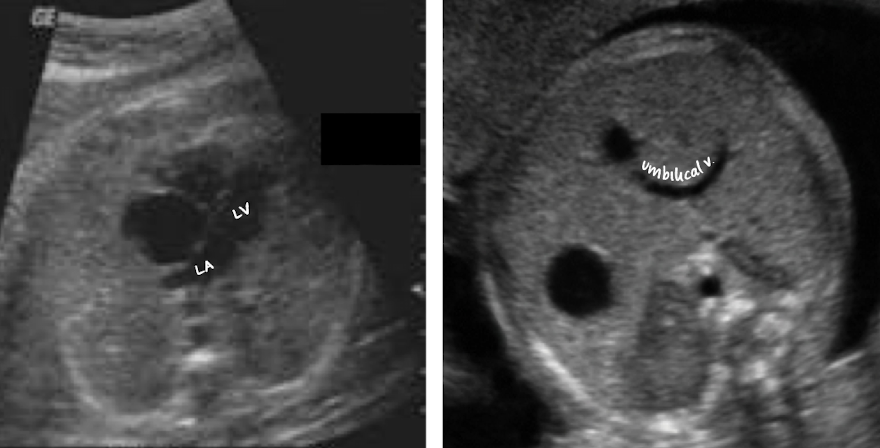

heart lies in mid chest, slightly to the left

located anteriorly and inferiorly

located posteriorly and adjacent to base of heart

which heart chamber is closest to the spine?

left atrium (LA)

T/F: LA is closest to the spine and AO

true

T/F: RV is most anterior to fetal body

LA is closest to AO and spine